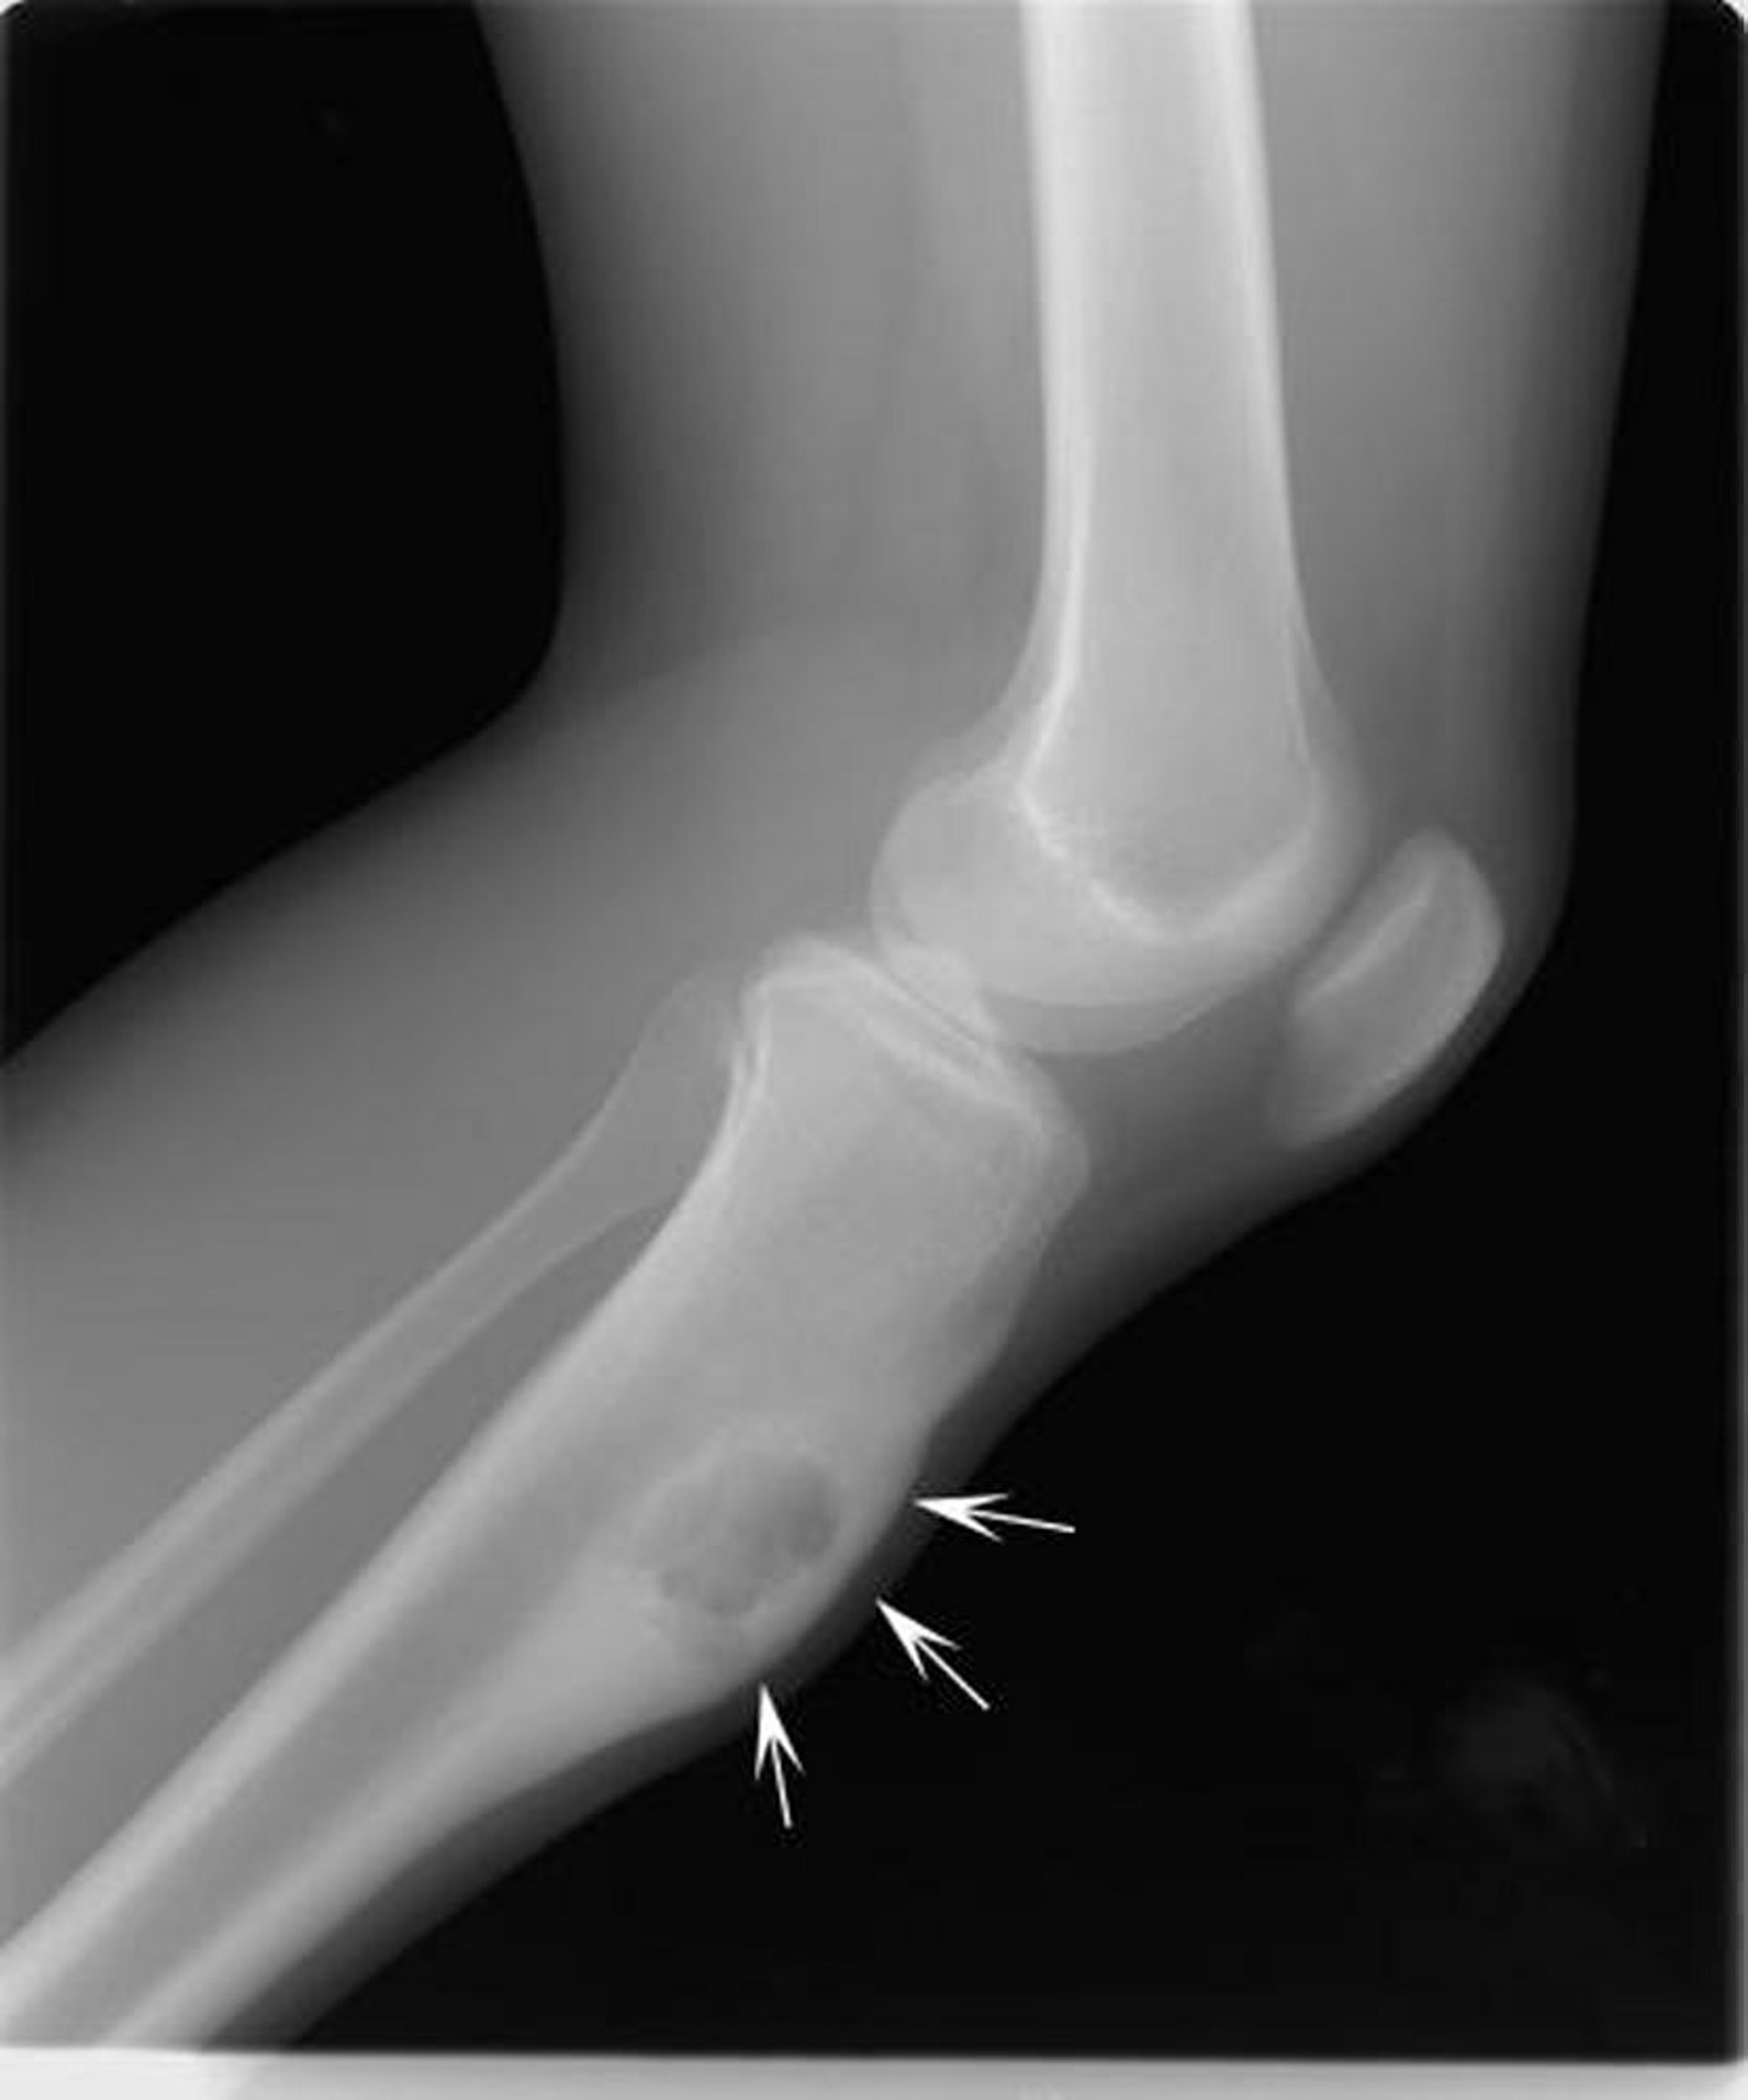

Esta radiografía de la rodilla muestra un fibroma condromixoide en la tibia debajo de la rodilla (flechas), que expande el hueso de la parte frontal.